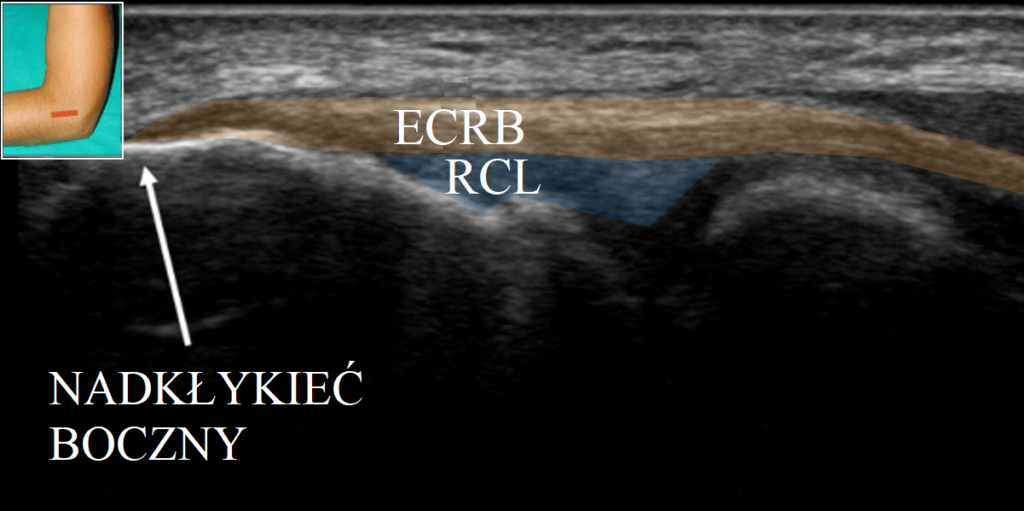

Termin „zapalenie ścięgna” używany jest powszechnie w celu opisu hipotetycznego, przewlekłego stanu zapalnego ścięgien okolicy nadkłykcia bocznego kości ramiennej. Jednakże badania histologiczne ścięgna nie wykazują obecności komórek stanu zapalnego. Zamiast tego tkanka charakteryzuje się zagęszczeniem fibroblastów, hiperplazją naczyń krwionośnych i dezorganizacją kolagenu na skutek zaburzonego gojenia mikrouszkodzeń ścięgna. Najczęściej do uszkodzenia dochodzi na wspólnym przyczepie ścięgna do kości, mięśnia prostownika promieniowego krótkiego nadgarstka (ECRB) i prostownika wspólnego palców (EDC) w miejscu, w którym nie można odróżnić ich od siebie histologicznie. Innym obszarem, w którym zachodzą mikrouszkodzenia, jest więzadło poboczne promieniowe (RCL), które jest w bliskim kontakcie z ECRB (zdj. 1).